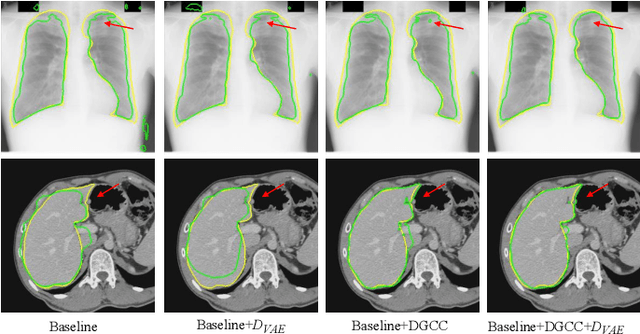

Despite that deep learning has achieved state-of-the-art performance for medical image segmentation, its success relies on a large set of manually annotated images for training that are expensive to acquire. In this paper, we propose an annotation-efficient learning framework for segmentation tasks that avoids annotations of training images, where we use an improved Cycle-Consistent Generative Adversarial Network (GAN) to learn from a set of unpaired medical images and auxiliary masks obtained either from a shape model or public datasets. We first use the GAN to generate pseudo labels for our training images under the implicit high-level shape constraint represented by a Variational Auto-encoder (VAE)-based discriminator with the help of the auxiliary masks, and build a Discriminator-guided Generator Channel Calibration (DGCC) module which employs our discriminator's feedback to calibrate the generator for better pseudo labels. To learn from the pseudo labels that are noisy, we further introduce a noise-robust iterative learning method using noise-weighted Dice loss. We validated our framework with two situations: objects with a simple shape model like optic disc in fundus images and fetal head in ultrasound images, and complex structures like lung in X-Ray images and liver in CT images. Experimental results demonstrated that 1) Our VAE-based discriminator and DGCC module help to obtain high-quality pseudo labels. 2) Our proposed noise-robust learning method can effectively overcome the effect of noisy pseudo labels. 3) The segmentation performance of our method without using annotations of training images is close or even comparable to that of learning from human annotations.